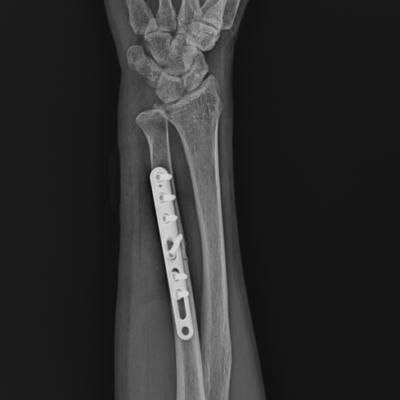

Wrist Fractures

Common Procedures – Carpal tunnel release. De Quervain's release. TFCC repair. fracture fixation. ulnar shortening osteotomy. etc.